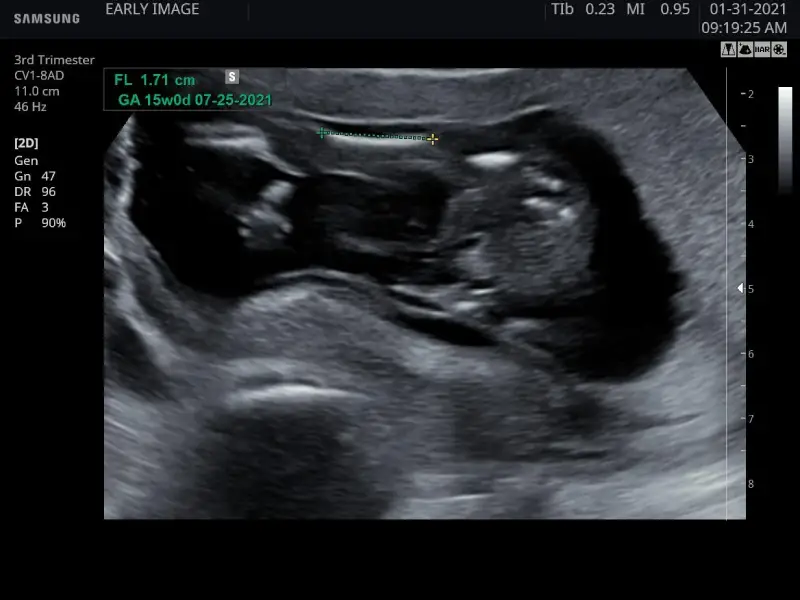

Using the very latest technology available in Ultrasound scanners, Realistic Vue, we are able to accurately confirm a baby’s sex, anytime, after your 14th week.

At Early Image, there are no rushed appointments and no one waiting behind you so we can take all the time we need to wait until baby moves into a position where we can see the gender for certain.

Check baby’s due date